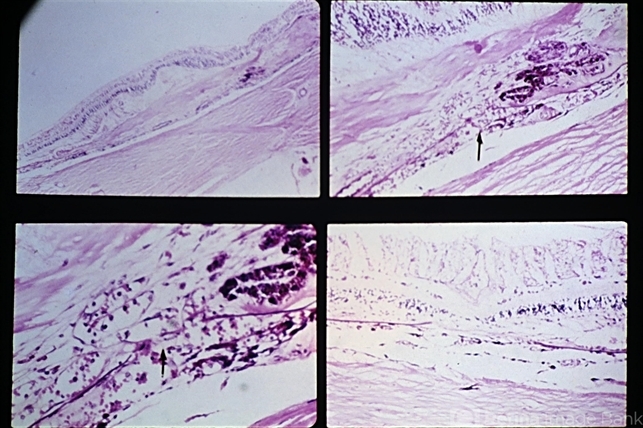

- disciform macular lesion, pseudoxanthoma elasticum (PXE), angioid streaks

- Macular disciform lesion in a 73-year-old man with angioid streaks and pseudoxanthoma elasticum. The streak is subjacent to the scar and is the point at which choroidal vessels (arrows) extend internally. The same streak closer to the disc is shown in the lower right view.